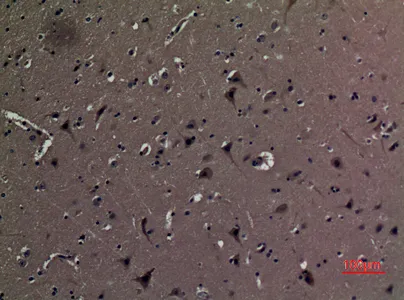

Adenosine A2A-R Rabbit Polyclonal Antibody

Cat: APRab06622

Size1:50μl Price1:$118

Size2:100μl Price2:$220

Size3:500μl Price3:$980

Size2:100μl Price2:$220

Size3:500μl Price3:$980